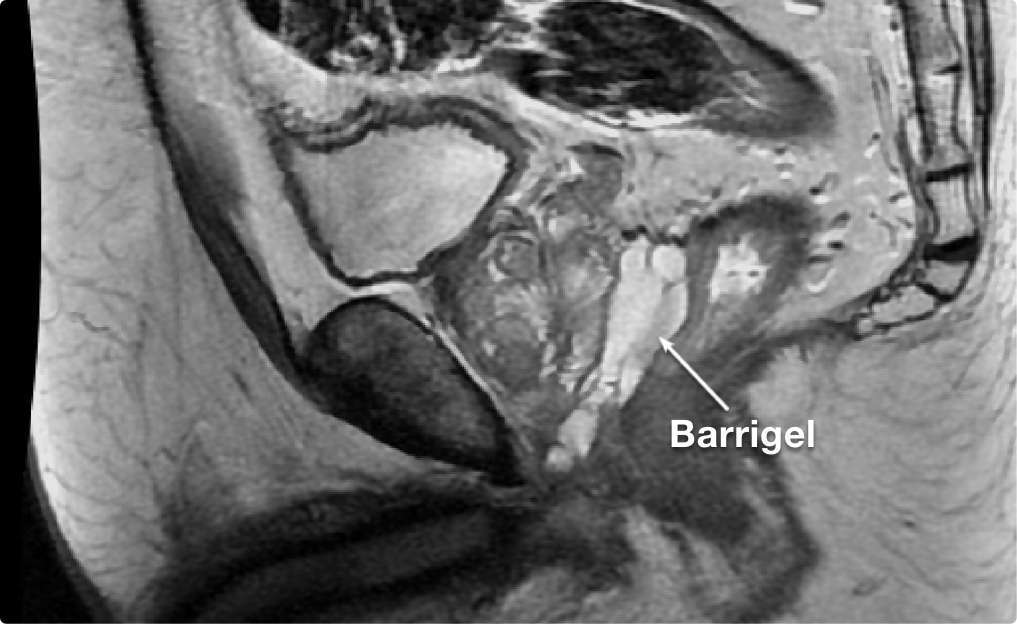

STABILITY MATTERS

STABILITY

MATTERS